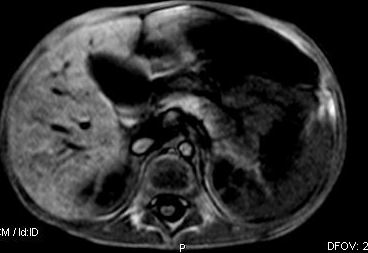

标题: V0176(MRI):小儿发热,肝脾大,肝内病变 [打印本页]

标题: V0176(MRI):小儿发热,肝脾大,肝内病变

5岁,2006年8月曾行阑尾炎手术,现发热半年